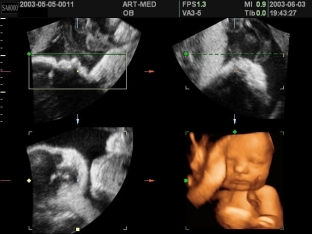

У плода-донора на тлі плацентарної недостатності внаслідок крововтрати та гіпоксії розвивається гіповолемія, а плід-реципієнт страждає від серцевої недостатності, що виникає внаслідок гіперволемії. Ультразвукове дослідження дозволяє діагностувати синдром фето-фетальної гемотрансфузії. Специфічними ознаками цього синдрому є такі ехографічні дані:

- виражена багатоводдя та великих розмірів сечовий міхур з поліурією у плода-реципієнта;

- практично повна «відсутність» сечового міхура та анурія у плода-донора.